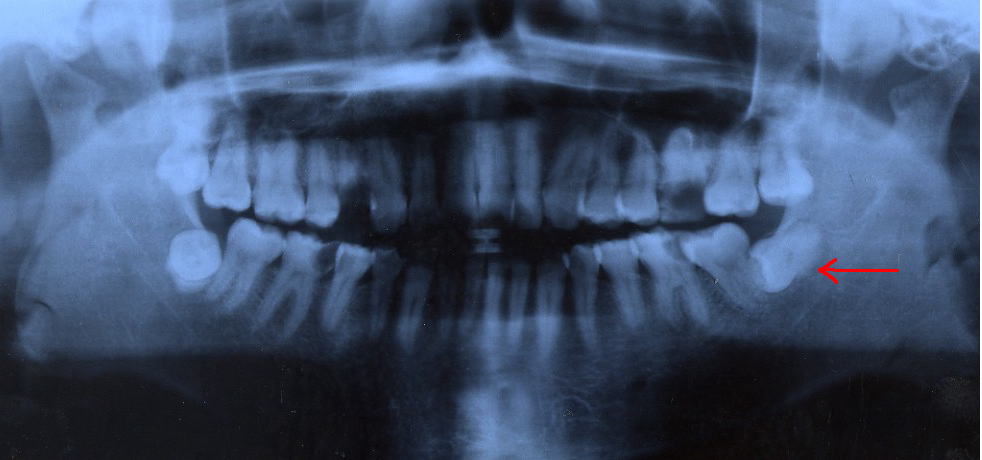

症例1 |

左下顎水平埋伏歯に起因する智歯周囲炎により、顔面腫脹、開口障害、嚥下障害を主訴に受診。

当初、局所洗浄と抗生剤の内服を行っていましたが疼痛著しく、腫脹の瀰漫性増大をきたしました。

そのため抗生剤を点滴静注し、消炎をはかりました。

消炎後4週間目に左下水平埋伏智歯の抜歯を行いました。